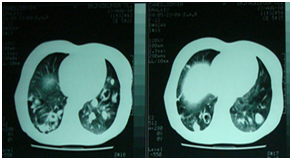

A 23 year-Old Iranian female patient presented with a six months history of fever, chest and abdominal pain, loss of appetite, weight loss, cough, night sweating and dyspnea was referred to our hospital. Physical examination revealed fever (39 centigrade), blood pressure 110/60 and coarse crackles at middle and lower area of both lungs. Abdomen was soft but a budging was seen in lower abdomen near the suprapubic region. Others organ, upper and lower extremity was normal. There was bilateral multiple nodular lesions at his chest X-ray. In hospital she takes ceftriaxone 2Gr and clindamycin 600mg twice daily. US of abdomen and pelvic was obtained and showed a cystic–solid lesion in the pelvic and in the liver. Computed tomography (CT) scan of the chest, abdomen and pelvic with IV contrast was obtained and showed multiple cavitary and solid-cystic mass lesions was showed in both lungs and the size of lesions were various in diameter. The lesions were located in the central and peripheral zone of both lungs (Figure 1). The abdomen and pelvic CT–scan showed solid-cystic mass in the pelvic and liver Radiologist finding and differential diagnosis was inflammatory lesion as Wegener granuloma, septic emboli, sarcoidosis and pulmonary metastasis from ovarian malignancy (Figure 2). Two days after admission, fever dropped and general condition of the patient becomes better. All lab date was normal except (ESR=40(0–20mm/h.CRP=22(0–5mg/L), WBC=16000). Fibroptic bronchoscopy was performed. Endobronchial lesion was not observed and bronchial lavage was obtained, Pathology examination of the bronchial lavage was normal, all other biochemical tests (CEA, ACE, RF, CA-125, hydatid tests and rheumatological tests) were normal. Laparatomy was performed ,the pelvic mass was excised and mass was opened, laminated membrane of hydatid cyst was seen, the lesion of liver was aspirated and fluid was clear, the mass was opened carefully and laminated membrane was seen (Figure 3) (Figure 4). With left mini anterolateral thoracotomy at 4 thintercostal space, chest wall was opened multiple nodules was palpable the big one was resected as wedge resection, the specimen was opened, laminated membrane was exposed (Figure 5). Chest tube was inserted and chest wall was closed in layers. Second post operative day, Albendazole was started at a dose of 10mg/kg/day for three cycle of 28days with 14days interval. Pathologist’s repot was hydatid cyst of lung in all three specimens (Figure 5). Patient was discharged in good condition 5days postoperative in the six months follow -up time there was no increased the size of both pulmonary nodules.

Figure 1 CT scan of the chest Show bilateral multiple nodules at both lungand cavitation.

During the growth , the cysts of lung may rupture in the tracheobronchial system or pleural space and patients complain of cough, expectoration of membranes, dyspnea, hemoptysis, and chest wall pain.1‒4 But in most uncomplicated cases of lung cysts are incidental finding or the patient may presents with dry cough, dyspnea, and chest pain.2‒4,8 The most common complication of pulmonary hydatid cyst is a secondary bacterial infection.2‒4,8 Infection resulting difficulty in differentiation it from an abscess or neoplasm lesions.3,4 Our case presented with fever, productive cough, dyspnea, chest pain and night sweating and this clinical presentation of our case mimicked a pulmonary infection such as tuberculosis or pulmonary abscess or pulmonary metastasis. Pelvic ultrasound has a low cost and a high sensitivity and constitutes the method of choice for pelvic and liver hydatid cysts.2,3,9 Pelvic and abdominal computed tomography allows to show the features, anatomic localization and extension of cystic masses. Pelvic magnetic resonance imaging (MRI) may be useful to recognize differential diagnosis of some tumor lesion in pelvic which including myxoid tumor such as myxoidneurofibroma and angiomyxoma(tun), Chest radiographs are useful to detect associated pulmonary hydatid cyst.9,10 In our case, pelvic hydatid cyst diagnosis was suggested by ultrasound CT-scan. In our case, hydatid serology test was not performed .The optimal treatment of pelvic hydatid cyst remains surgery. In our case we performed a diagnostic laparotomy, during exploration, we find a cystic–solid lesion of ovarian, after aspiration and evacuation, laminated membrane of hydatid cyst presented, lesion on the liver was aspirated, evacuated, hydatid cyst membrane was presented. With a mini thoracotomy a wedge resection of left lung was performed, daughter cyst and laminated membrane was presented from this lesion. The definitive diagnosis obtained from pathologist in all three specimens. Postoperatively, Albendazole was started at a dose of 10 mg/kg/day for three cycles of 28days with 14days interval. Patient was discharged in good condition 5days postoperative in the six months follow-up time there was no increased the size of both pulmonary nodules.